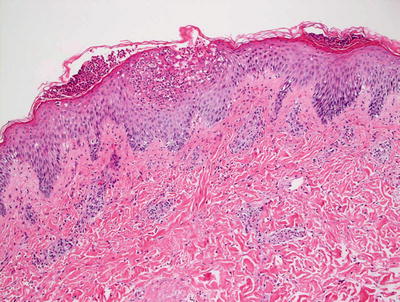

3.5.2 Histology

AGEP is uncommon in children, but when it occurs, shows the same histologic changes as have been reported in adults [35]. Subcorneal pustules comprised of neutrophils are present within a slightly spongiotic epidermis (Fig. 3.12). Parakeratosis is infrequent, except in older lesions. The granular layer persists and acanthosis is not a common finding. Within the dermis, there is a mixed inflammatory infiltrate that consists of neutrophils, eosinophils, and histiocytes [36] (Fig. 3.13).

Fig. 3.12

AGEP demonstrates subcorneal and intraepidermal neutrophilic abscesses. There is focal spongiosis and a mild, mixed superficial dermal perivascular infiltrate